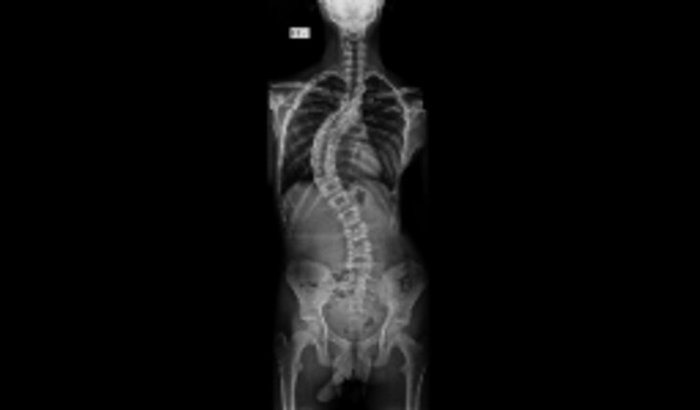

Eu me chamo Pablo ferreira tenho 14 anos e a um 1 ano e seis faço tratamento de escoliose,E a minha escoliose é progressiva,Me indicaram colete porque só posso fazer a cirurgia aos 17 anos e com isso se eu fica sem colete o grau pode aumenta por isso criei essa vaquinha online,No momento meus pais nao tem condições de arca com esse valor para meu tratamento, Desde de ja eu agradeço pela ajuda e que Deus possa abençoar cada um que me abençou .